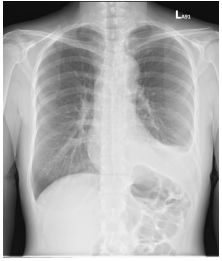

2. A 27-year-old woman had productive cough for one month.